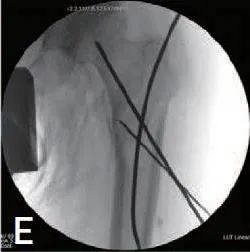

确定大转子外侧的钉入点,并在转子尖端近端约 5 cm 处做一个切口。插入导丝并进行近端铰孔(图 1E)。然后轻柔地用锤子敲击钉子,取出导丝。钉完全插入后,重新检查骨折复位状态。

图1E 在骨折间隙之间插入额外的2.4mm克氏针,并将导丝插入钉入点。